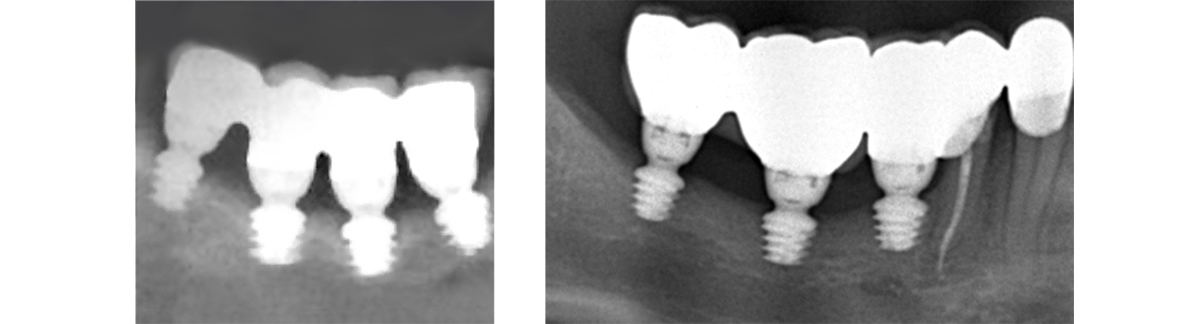

L’implant twinKon® est un implant type Tissue Level.

L’implant twinKon® est de type Tissue Level, généralement apprécié pour leur capacité à préserver le capital osseux péri-implantaire(1), mais également pour leur accessibilité prothétique en bouche. Le twinKon® est un implant qui sera particulièrement apprécié en secteur mandibulaire présentant une atrophie allant de modérée à sévère.